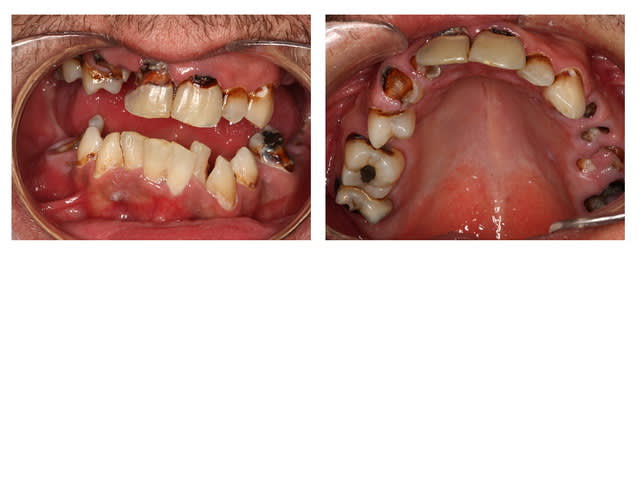

Joli aussi ça non ???

Pp ;-)

Non hélas patiente de 28 ans...

Si c était Pp , vu son grand âge, ce serait moins grave

Néanmoins patiente traitée ...